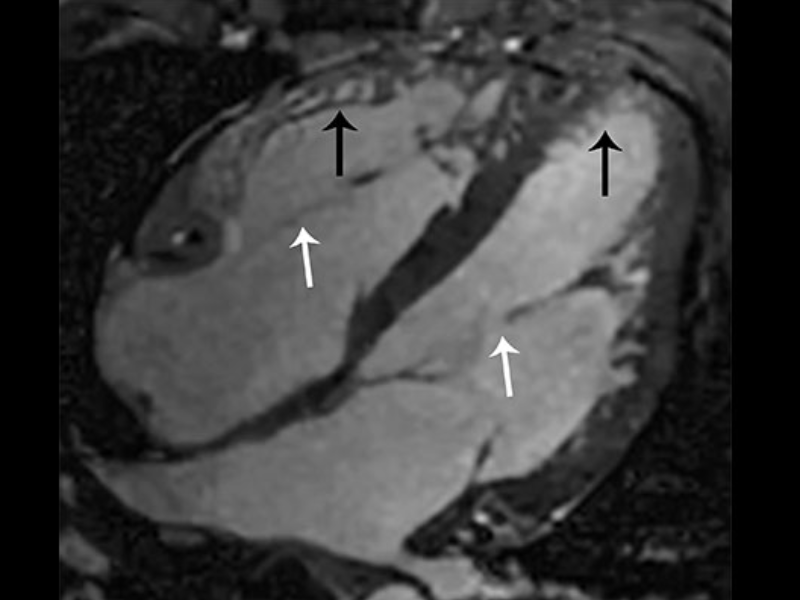

4 chamber cardiac cine